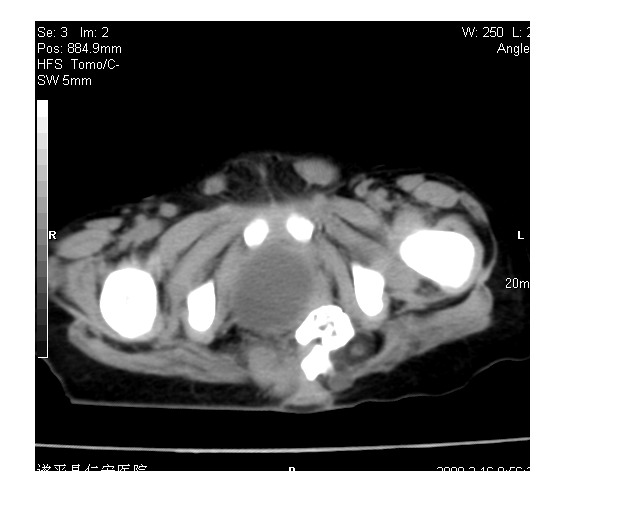

以下是引用lkc8963在2008-3-16 12:49:00的发言:[br]盆底巨大混杂密度肿块,富含多种组织成分包括脂肪/液体/软组织/钙化,边界清楚,向前压迫肠管及膀胱,向后突入骶尾部皮下脂肪层,首先考虑畸胎瘤,诊断时需要与脊柱裂/囊性淋巴管瘤等区别。